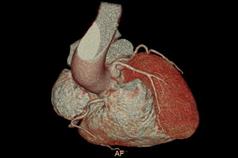

PAÜ Hastaneleri Radyoloji Anabilim Dalı Öğretim Üyesi Doç. Dr. Vefa Çakmak yaptığı açıklama da şunları söyledi: “Pandemi döneminde hayatımıza daha sık giren bilgisayarlı tomografi (BT), günümüzde tanı ve tedavi süreçlerinde hayati önem taşıyan bir görüntüleme yöntemi olarak kullanılmaya devam ediyor. Radyasyon içeren bu teknoloji, pek çok organın ayrıntılı şekilde incelenmesini sağlarken, acil durumlarda hızlı teşhis imkânı sunarak hayat kurtarıcı bir rol üstleniyor. Özellikle kanserin tanı ve takibinde, trafik kazaları, beyin kanamaları, kırıklar ve büyük cerrahiler öncesinde önemli bir yer tutuyor. BT ile kalbi besleyen damarların detaylı şekilde görüntülenmesi mümkün hale geliyor. Halk arasında ‘sanal anjiyo’ olarak bilinen bu yöntemle, kalpte işlem gerektiren damar tıkanıklıkları erkenden saptanabiliyor. Böylece hastalar, gereksiz klasik anjiyo işlemlerinden korunuyor. Aynı anda kalp duvarları, kalp içindeki pıhtı ya da tümör gibi oluşumlar ve ritim bozukluğuna neden olabilecek yapılar da değerlendirilebiliyor. Ayrıca, bu çekimler sırasında düşük dozla akciğer görüntülemesi de yapılarak yapısal akciğer hastalıkları, akciğer kanserleri ve göğüs kafesiyle ilgili kemik problemleri de tespit edilebiliyor. Çekim öncesinde hastanın böbrek fonksiyonlarını korumak amacıyla kreatin ve GFR gibi kan testleri yapılıyor. Hastanın mevcut hastalık öyküsü ve ilaç alerjileri sorgulanıyor. Kaliteli bir görüntü elde edebilmek için kalp atım hızının dakikada 70 civarına düşürülmesi gerekebiliyor; bu durumda nabız düzenleyici ilaçlar kullanılabiliyor. İşlem sırasında hasta monitörize ediliyor, göğüs bölgesindeki metal eşyalar çıkarılıyor ve yaklaşık 10–15 saniyelik nefes tutması isteniyor. Kardiyak BT çekimi 4–10 saniye sürüyor ve görüntülerin değerlendirilip raporlanması genellikle aynı gün içinde tamamlanıyor.”